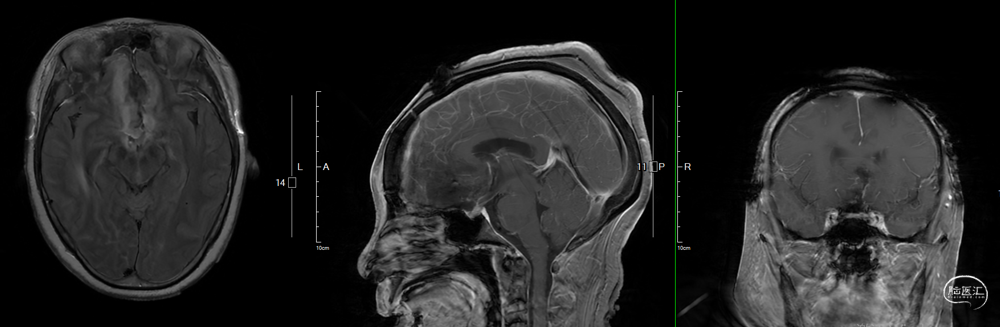

术后影像学

![]()

头部MRI提示:影像学全切,脑积水得到明显好转,实性部分未见显影,垂体组织保留良好。